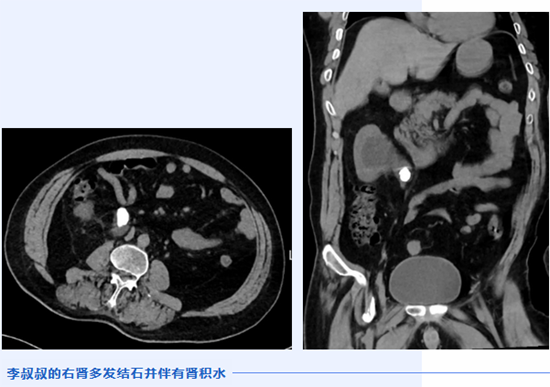

李叔叔是一位因车祸导致外伤术后3年的患者,开颅手术后伴有偏瘫以及言语和认知障碍。为了尽快康复,他的爱人福阿姨和儿子带着他在医院进行长期的康复锻炼。没多久肢体功能便产生了积极的变化,但在长期卧床的这段日子里,李叔叔偶尔会出现腰痛、尿液异常等表现。主管医生为他安排了CT检查,结果发现其右肾长有多个结石。经北京积水潭医院贵州医院泌尿外科主任翟建坡会诊,并与家属沟通后,决定将李叔叔转到外科针对肾结石展开治疗。

经外科检查发现,在李叔叔右肾的多个结石中,有一个结石较大并且阻塞输尿管,造成右肾积水,右肾周还有少许的渗出。如果不及时处理可能会导致右侧肾功能衰竭,或者感染加重,诱发脓毒血症危及生命。翟建坡评估他的病情后,认为经皮肾镜碎石取石术是最适合李叔叔的治疗方式。